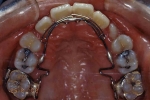

マルチブラケット終了時

|